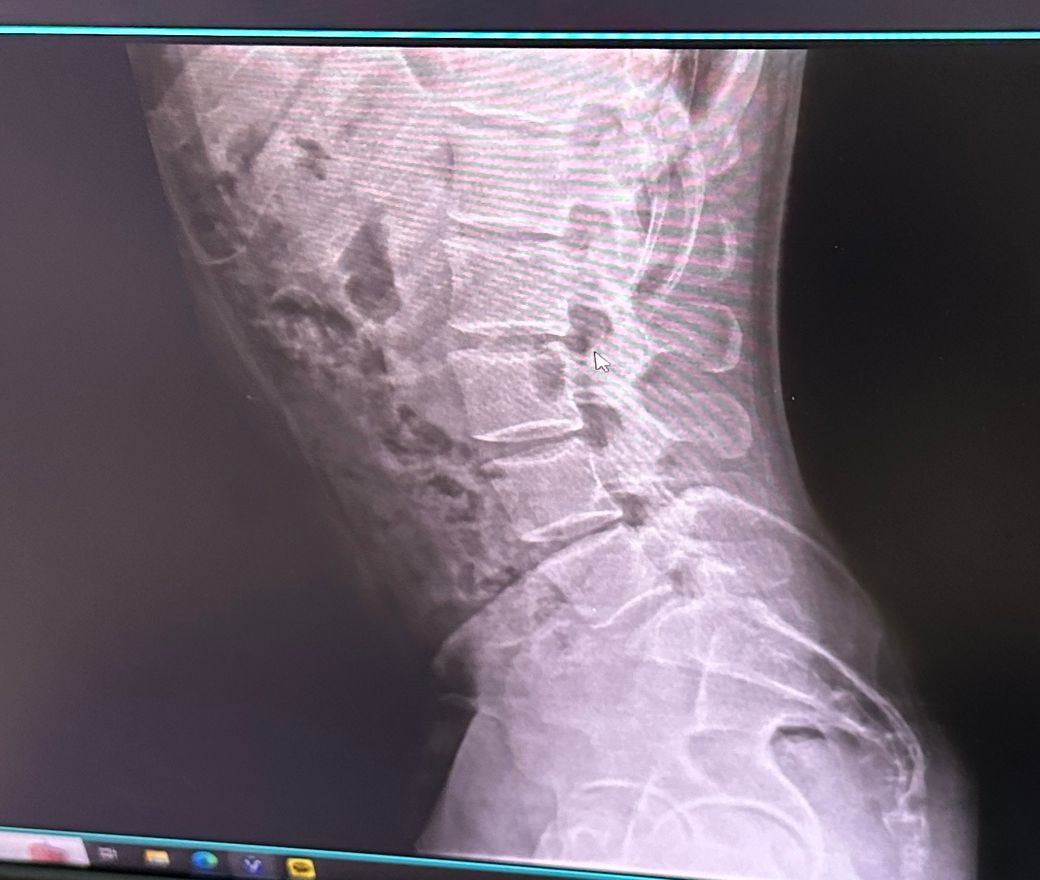

• 2번 째 사진

측만증이 다양한 원인이 있지만 엑스레이 상에서 보아도 측만증이 있어보이긴 합니다. 근데 측만증이라는게 선천적일수도 있고 후천적일 수도 있고 이에따라 치료법이 다르고.. 또한 내가 등이 아프면서 안아프게 하려고 몸을 꼬니까 측만증이 있는것처럼 보일 수 있습니다.

사진상으로 많은걸확인할수는없지만 지금가지고있는 측만증의경우 자세적인문제가있을수있는데요 잠을자거나 휴식을취할때 엎드리거나 만세를하고있는동작은 목어깨나 허리, 몸에 부담을줄수있기때문에 추천하지않습니다